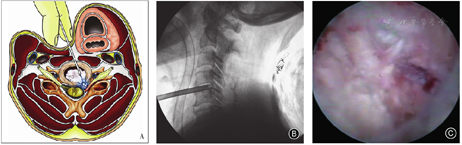

预防措施包括术中首先要用两指法推移内脏鞘和血管鞘,扪及椎体和椎间盘表面,食指和中指分别向内、外侧推开以保护食管和颈部血管,术中透视观察气管阴影可帮助确定气管、食管复合体偏离中线的位置;在两手指之间穿刺,最好接近椎间盘表面的中部进针,避免损伤颈长肌及其表面交感链,穿刺角度不宜太大(一般≤15°),以免损伤对侧椎动脉等组织;避免使用环锯等锐性器械扩张,以免损伤周围血管包括小动脉和食管等,术中X线透视监视穿刺和置管位置(图1)。

胸椎PTED受肋骨和胸廓的影响,有引起气胸的风险。因胸椎间盘和椎体后缘呈凹形,硬膜囊前缘可超过侧位X线片椎体后缘线,而且脊髓耐受性差,不能像腰椎那样将工作套管置入椎管内。术前要根据CT和MR轴位像测量并设计穿刺路线,即自椎弓根中部的纤维环后缘经关节突外缘与肋骨头之间至皮肤的延长线,穿刺、置管必须保持在肋骨头后侧以避开胸腔。我们采用的穿刺点一般距离中线约5~7 cm,穿刺针平行于椎间隙,但轴位上更倾斜,可达45°左右。为防止损伤脊髓,应避免穿刺和扩张、置管进入椎管内,正位X线透视穿刺针尖到达椎弓根中部时,侧位X线透视应在椎体后缘,仅去除关节突外缘即可,目的是安置工作套管而不是关节突成形或进入椎管。置管首先进入椎间盘后部,进行间接减压,可用激光等松解致压物,使突出物回纳,在经皮内镜直视下调整套管,摘除向后突出的髓核组织,达到硬膜囊充分松弛和隆起。所以,我们认为胸椎PTED不能采用将工作套管置入椎管内的"TESSYS(transforaminal endoscopic spine system)"技术,而应采用将工作套管置入突出物基底部或椎间隙后部的"YESS(Yeung endoscopic spine system)"技术。